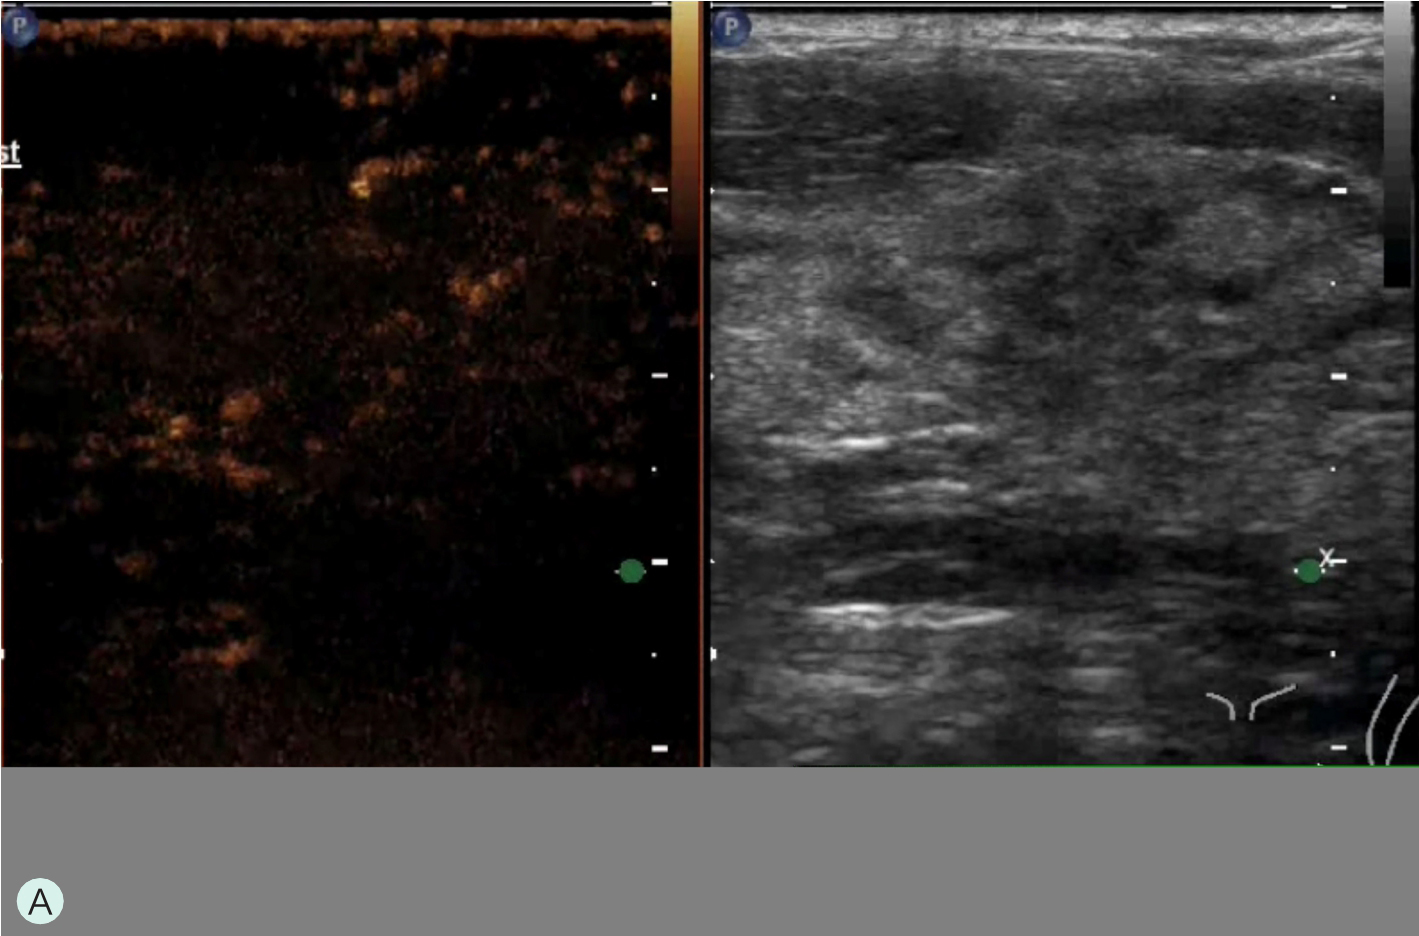

图1-4-3 CEUS时不同乳腺腺体增强强度

A.CEUS背景极少强化;B.CEUS背景轻度强化;C.CEUS背景中度强化;D.CEUS背景重度强化